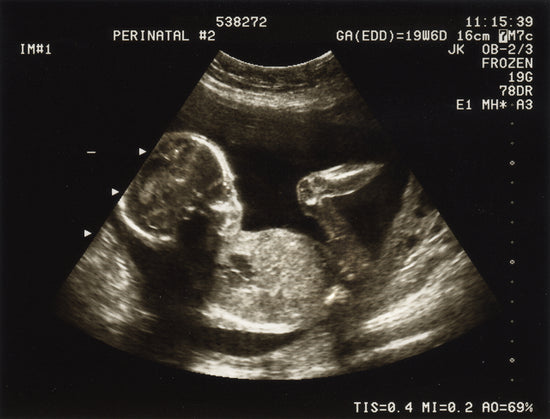

Recent news has been filled with stories linking Ozempic use to pregnancies, highlighting two key issues. Firstly, weight loss drugs such as semaglutide and tirzepatide are associated with increased fertility and higher pregnancy rates. Secondly, there is a significant concern about the lack of information on their effects during early pregnancy.